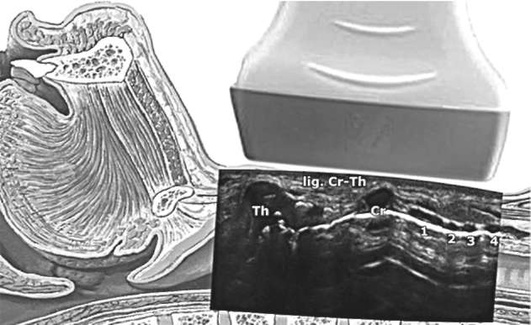

Методика выполнения хирургической крикотиреотомии при непальпируемой перстнещитовидной мембране:

• после обработки кожи и обкладывания стерильными салфетками ниже щитовидного хряща по средней линии шеи пальпируют хрящевые структуры гортани;

• при наличии возможности верифицируют перстнещитовидную мембрану с помощью ультразвука (рис. 2.58);

• удерживая гортань, выполняют вертикальный разрез 4-6 см от выступающей части щитовидного хряща вниз;

• пальцами разводят ткани до обнаружения перстнещитовидной мембраны;

• большим и указательным пальцами недоминирующей руки осуществляют фиксацию гортани, доминирующей рукой скальпелем выполняют горизонтальный разрез мембраны;

• ротируют скальпель острым краем каудально для расширения просвета раны;

• осуществляя тракцию скальпелем в каудальном направлении, в трахею вводят буж и убирают скальпель;

• по бужу в трахею заводят эндотрахеальную трубку, раздувают манжету, подключают кислород;

• верифицируют положение трубки стандартным образом; трубку фиксируют.

pic 0068

Рис. 2.58. Ультразвуковая анатомия дыхательных путей: Th - щитовидный хрящ; Cr - перстневидный хрящ; lig. Cr-Th - перстнещитовидная мембрана; 1, 2, 3, 4 - кольца трахеи

Выполнение хирургической крикотиреотомии возможно также с помощью специальных наборов (традиционная открытая техника), которые содержат скальпель с фиксированной длиной лезвия, шприц для верификации попадания трубки в трахею с помощью аспирационной пробы, эндотрахельную трубку с раздуваемой манжетой диаметром 6 мм и проводником, трахеальный крючок (рис. 2.59).